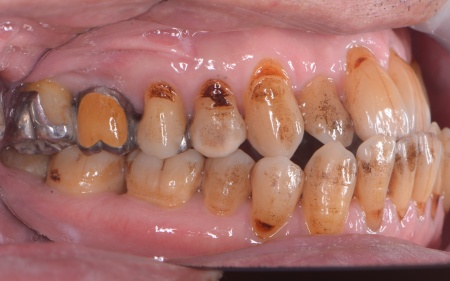

| 相談内容 | 「右上の奥歯がしみる」とご相談いただきました。 |

| カウンセリング | 拝見したところ、右上の奥歯には複数の歯をつないだ被せ物であるブリッジが入っていましたが、被せ物の内部で虫歯が再発していました。 レントゲンを撮影して詳しく調べた結果、虫歯は比較的大きく歯の神経に近い深さまで進行していることが確認できました。 このまま放置すると、神経に炎症が起こって強い痛みが出る、神経が死んでしまい歯を温存できなくなるといった可能性があります。 以上のことから、ブリッジを取り外して虫歯を治療する必要があると診断しました。 |